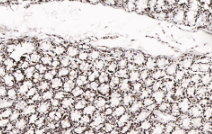

IHC    1/200-500